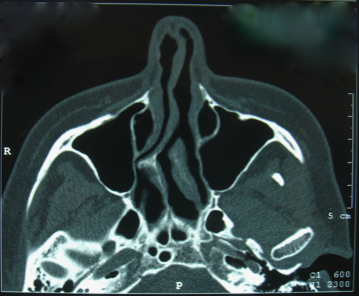

L’évaluation précise de la déformation nasale est appréciée par l’examen endonasal, mais également par un scanner des fosses nasales, en particulier après un traumatisme du nez ou une fracture du nez (FOPN).

photo déviation